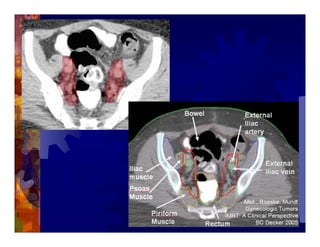

1) Intensity modulated radiation therapy (IMRT) is a technique that uses computer software to conform the radiation dose to the shape of the tumor, reducing dose to surrounding normal tissues and decreasing toxicity. 2) Numerous studies have shown IMRT provides better sparing of the small bowel, bladder, and rectum compared to conventional radiation for gynecologic cancers. 3) IMRT may allow dose escalation to high risk sites or involved nodes while maintaining normal tissue doses. Some studies have also investigated using IMRT as an alternative to brachytherapy boosts. 4) Clinical studies suggest IMRT results in low rates of acute gastrointestinal and genitourinary toxicity compared to conventional radiation for